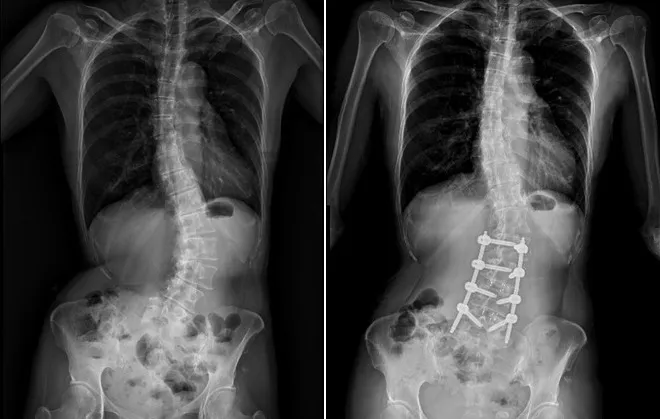

市醫微創脊椎中心助理副院長張建鈞醫師表示,患者因長期未治療,脊椎側彎角度已達48度,屬中重度退化性脊椎側彎,加上合併二尖瓣膜脫垂心臟病史,進行傳統開放式手術風險極高。經完整影像評估與跨科討論後,醫療團隊建議採取「微創前開3D導航矯正手術」,在不大幅破壞背部肌群的情況下,從側邊小切口進行矯正與支撐重建。

共同執行手術的骨科部副部長林琮凱醫師進一步說明,脊椎側彎是指脊椎向側面異常彎曲,並伴隨椎體旋轉變形,並非單純姿勢不良。醫學上以Cobb角度作為判斷依據,超過10度即可診斷為脊椎側彎。

55歲黃小姐接受3D導航微創矯正手術解決25年來脊椎側彎的毛病,特別向醫療團隊致謝。台中市醫提供